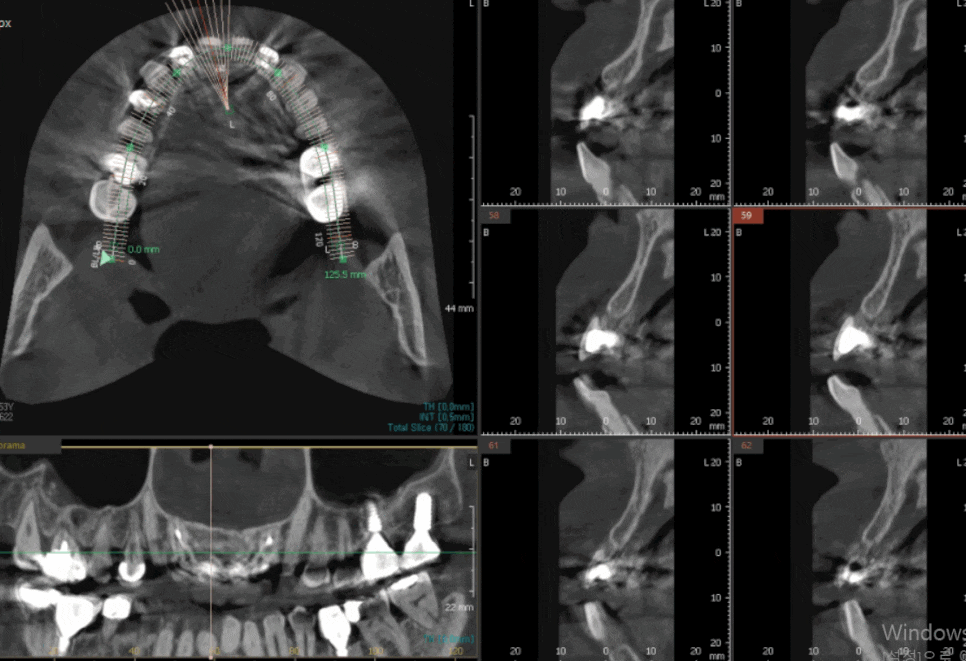

게다가 앞니 2개는 이미 오래전에 뽑은 상태라

뼈가 많이 흡수돼 있었습니다.

240622

임플란트를 심기에는 뼈가 너무 얇았죠.

환자분과 충분한 상의 후 브릿지로 진행하기로 했습니다.

양쪽 끝 치아는 뿌리만 남아 있었고,

내부는 충치가 진행되어 있었습니다.

어쩔 수 없이 발치 후 6개 브릿지로 진행하기로 했습니다.

양쪽 송곳니를 살짝 다듬어야 하는데,

여기서 고민이 생겼어요.

송곳니는 신경이 살아있는 치아라 너무 많이 깎으면 시릴 수 있습니다.

그래서 최소한만 삭제했는데,

이렇게 하면 다른 문제가 생깁니다.

환자분 아래 앞니도 원래 약간 앞으로 나와 있는 편이셨어요.